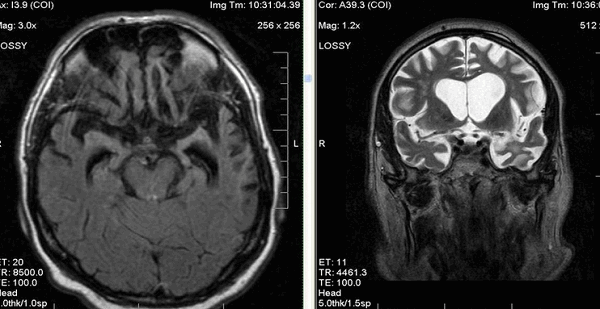

- МРТ головного мозга. В начальной стадии может соответствовать норме. В дальнейшем обнаруживаются атрофические изменения головного мозга, наиболее выраженные в мозжечке и подкорковых ганглиях. МРТ позволяет исключить рассеянный склероз, энцефалит, опухолевые процессы.

Атрофия головного мозга на МРТ

Магнитно-резонансная томография признана одним из наиболее информативных нейровизуализационных методов исследования. В ходе процедуры получают детальные послойные снимки головного мозга, позволяющие оценить соответствие органа нормам.

МРТ актуальна при диагностике посттравматических состояний, воспалительных, опухолевых, нейродегенеративных изменений. Одно из самых тяжелых нарушений, выявляемых с помощью томографии — атрофия головного мозга. Это хроническое прогрессирующее заболевание, сопровождающееся гибелью нейронов, уменьшением объема и плотности структур головного мозга.

Как выглядит атрофия головного мозга на МРТ?

Диффузная атрофия головного мозга с вентрикуломегалией

Явление дифференцируют с истинной гидроцефалией. Главный МРТ-признак атрофии головного мозга — пропорциональное расширение внутренних и наружных ликворных церебральных пространств, что указывает на уменьшение объема структур органа. Выраженность изменений оценивают с помощью церебро-вентрикулярного индекса (ЦВИ Эванса). Учитывают и другие отклонения в ткани головного мозга.

Симптомы патологии на МРТ-снимках:

увеличение ЦВИ Эванса;

расширение субарахноидальных борозд и щелей;

снижение плотности мозговой ткани;

дистрофия белого вещества;

уменьшение долей мозга в размерах.

В зависимости от локализации патологических изменений и степени вовлеченности структур атрофия может быть:

кортикальной (главный признак — инволюция коры на уровне лобных и височных долей);

мультисистемной или диффузной (очаги обнаруживаются сразу на нескольких участках);

генерализованной (изменения происходят во всех отделах органа).